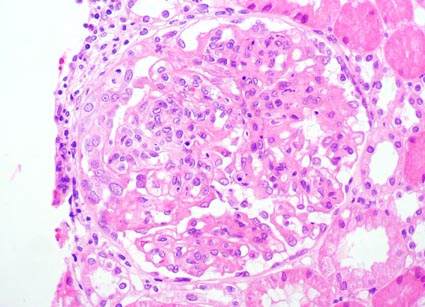

Observe las imágenes de la biopsia.

Figura 1.

H&E, X400.